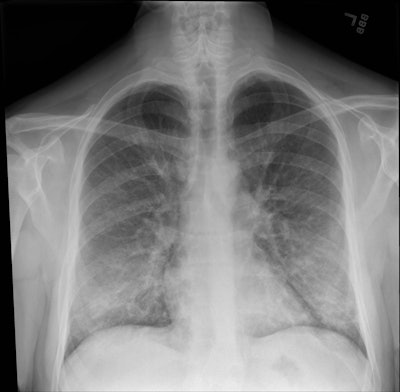

Chest radiographs revealed reductions in acute findings for most of the patients, confirming overall improvement, though 67% still showed residual abnormalities, such as bilateral interstitial and alveolar opacities or bronchial wall thickening.

The chest x-ray of a patient with vaping-associated lung injury shows lung opacities, densities, and whitish cloud-like areas common in unusual pneumonias, pulmonary edema, and lung inflammation. Image courtesy of Intermountain Healthcare.These findings are helping physicians recognize what lung injuries associated with e-cigarettes or vaping look like -- and helping them maintain a high degree of suspicion when they diagnose lung injuries in patients who've been vaping, Blagev noted.